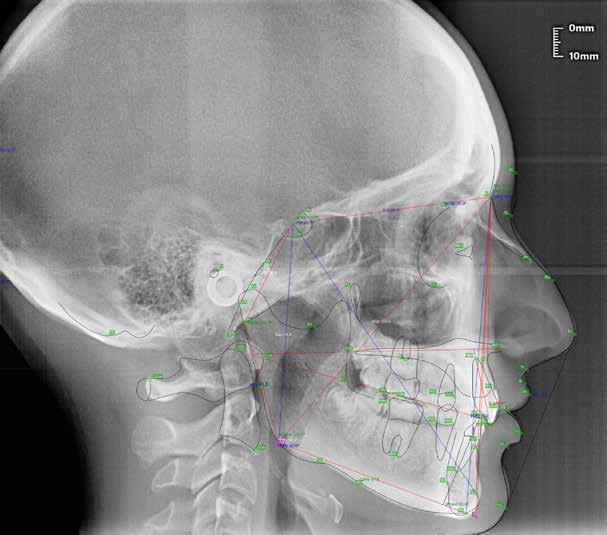

47 46 ESTETICA FUNZIONE POSTURA Valori cefalometrici a 10 anni : ANB ANB 2.70 Posizione del Mascellare SNA 78,70 Posizione della Mandibola SNB 76.0 Angolo Articolare SArGo 142,76 Angolo Goniaco ArGoMe 125,73 Angolo incisivo inf^Corpo madibolare IiMand 92,00 Angolo incisivo Sup^Base Cranica Ant. IsCran 96,00 Angolo Interincisivo II 130,0 53 _ Esame Cefalometrico a dieci anni. 54 _ Tabella dei valori cefalometrici a dieci anni. 55 _ Ortopantomografia di controllo a dieci anni. 56 _ Teleradiografia di controllo con evidente stabilità del caso dal punto di vista scheletrico/posturale.

> La documentazione a dieci anni mostra la stabilità del caso e

come l’occlusione, elastodonticamente individuata, costituisca anche la contenzione stessa. La paziente ha smesso di

Considerazioni

indossare l’apparecchio elastodontico dopo due anni e mezzo di terapia, conservando parametri occlusali e posturali in rapporto corretto tra loro.

Nel 2019 si è provveduto all’avulsione chirurgica degli elementi dentari 18, 28, 38 e 48.

Alla risoluzione della malocclusione scheletrica e dentale si associa un netto recupero della postura con conseguente miglioramento della curva cervicale, come è possibile verificare nella teleradiografia finale.